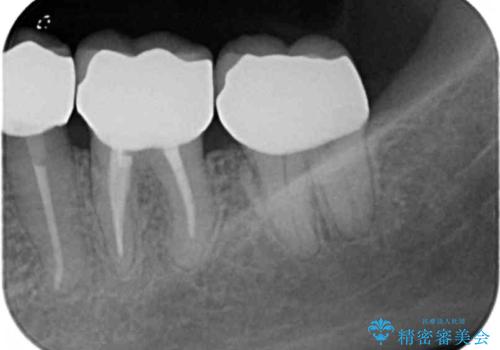

- 虫歯治療、老朽化した銀歯や詰め物 コンポジットレジンのやりかえを希望され来院されました。

クラウンやレジン下に再発していた虫歯を丁寧に除去したのち、歯ぐきの腫れが改善が見られないため歯周外科を行い歯ぐきの状態を整えたのちにジルコニアクラウンを製作していきます。

クラウン治療を行う場合歯ぐきの腫れが、クラウン製作の精密さにおいて問題点となることがあります。

このような場合、歯周外科を行うことでクラウン周囲の歯茎の状態を整備し精度に優れる治療を行うことができます。